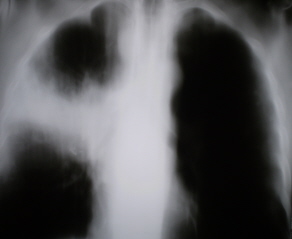

На рентгенограммах органов грудной полости, произведенных в стандартных проекциях – прямая и правая боковая (иллюстрации № 1 и № 2) определяется снижение прозрачности легочной ткани за счет инфильтрации в верхней доле правого лёгкого, с преимущественным поражением заднего и переднего сегментов. Также определяется снижение прозрачности легочной ткани в средней доле в виде очагов сливного характера с некоторым объёмным уменьшением. Плевра в главной и малой междолевых щелях плевра утолщена.